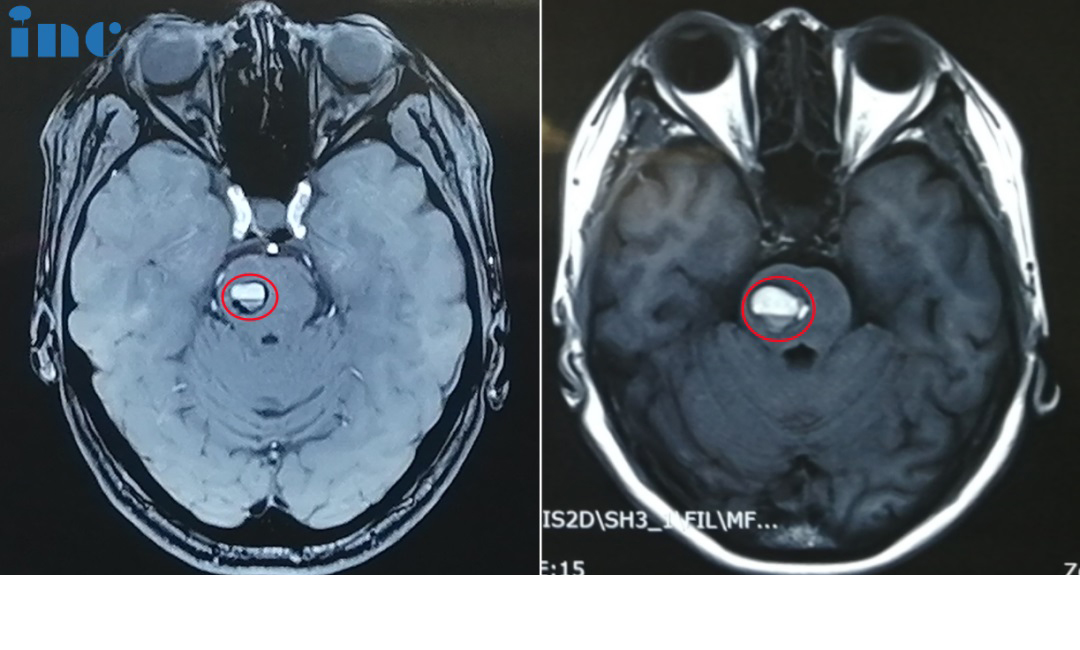

腦干海綿狀血管瘤——術(shù)前影像

術(shù)前影像:面神經(jīng)受壓迫